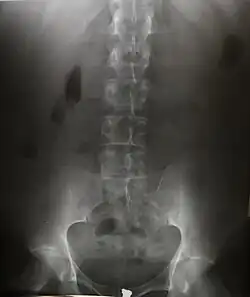

Projectional radiography

The creation of images by exposing an object to X-rays or other high-energy forms of electromagnetic radiation and capturing the resulting remnant beam (or "shadow") as a latent image is known as "projection radiography". The "shadow" may be converted to light using a fluorescent screen, which is then captured on photographic film, it may be captured by a phosphor screen to be "read" later by a laser (CR), or it may directly activate a matrix of solid-state detectors (DR—similar to a very large version of a CCD in a digital camera). Bone and some organs (such as lungs) especially lend themselves to projection radiography. It is a relatively low-cost investigation with a high diagnostic yield. The difference between soft and hard body parts stems mostly from the fact that carbon has a very low X-ray cross section compared to calcium.